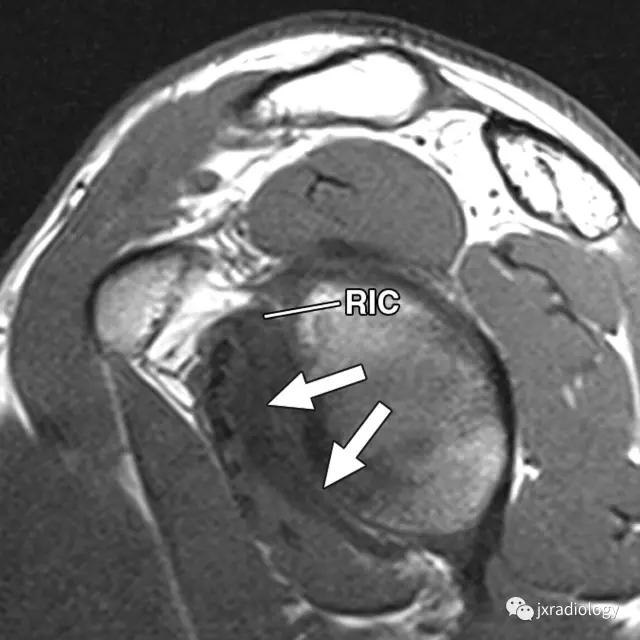

2、肩袖间隙周边稳定肱二头肌腱长头(LBT) 的滑轮结构创伤性病变 , 如肩胛下肌腱、SGHL-MCHL 复合体、外侧CHL等损伤 。

病例图示:

文章插图